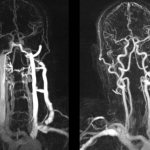

The cerebral hemispheres are the most massive part of the brain. They cover the cerebellum and brain stem. The cerebral hemispheres make up approximately 78% of the total brain mass. During the ontogenetic development of the organism, the cerebral hemispheres develop from the telencephalon of the neural tube, therefore this part of the brain is also called the telencephalon. The cerebral hemispheres are divided along the midline by a deep vertical fissure into the right and left hemispheres. In the depths of the middle part, both hemispheres are connected to each other by a large commissure - the corpus callosum. Each hemisphere has lobes : frontal, parietal, temporal, occipital and insula. The island, or the so-called closed lobule, is located in the depths of the lateral sulcus. The insula is separated from adjacent neighboring sections by a circular groove. The surface of the insula is divided by its longitudinal central groove into anterior and posterior parts. The lobes of the cerebral hemispheres are separated from one another by deep grooves. The most important are three deep grooves : central (Rolandic), separating the frontal lobe from the parietal lobe; lateral (Sylvian), separating the temporal lobe from the parietal, and parieto-occipital, separating the parietal lobe from the occipital lobe on the inner surface of the hemisphere. Each hemisphere has a superolateral (convex), inferior and internal surface. Each lobe of the hemisphere has cerebral convolutions separated from each other by grooves. The top of the hemisphere is covered with a cortex - a thin layer of gray matter, which consists of nerve cells. Under the cortex is the white matter of the hemispheres; it consists of processes of nerve cells - conductors. Functions: The frontal cortex of the cerebral hemispheres also takes an active part in the formation of thinking, the organization of purposeful activities, and long-term planning. The cortical part of the sensitive analyzer is localized in the parietal lobe. The temporal lobes play an important role in organizing complex mental processes, in particular memory. The function of the occipital lobe is associated with the perception and processing of visual information, the organization of complex processes of visual perception. A taste analyzer is projected in the island. Since the olfactory analyzer plays an important role in the regulation of emotions, its central section is classified as the limbic system. The corpus callosum connects the phylogenetically youngest parts of the hemispheres and plays an important role in the exchange of information between them. Symptoms of damage to the cerebral hemispheres For damage to the right side